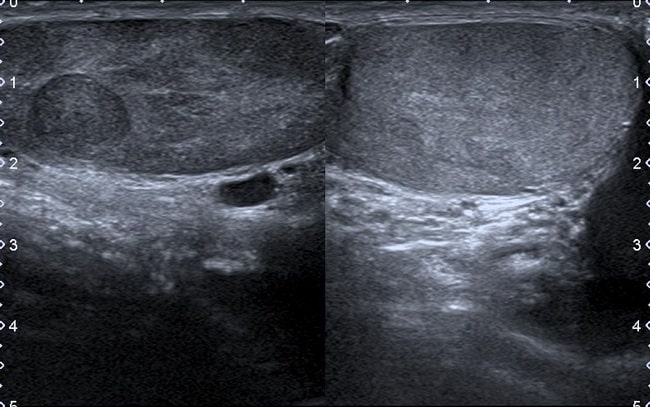

Ultrasonografi atau USG testis merupakan pencitraan noninvasif yang umum dilakukan untuk mendiagnosis undesensus testis, orchitis, epididimitis, testis asimetri, torsio testis, dan penyakit endokrin pada anak-anak. Pada orang dewasa, USG testis juga umum dilakukan untuk mendiagnosis berbagai abnormalitas testis.[1,2]

USG testis dapat mengidentifikasi lesi intratestikuler dan ekstratestikuler, membedakan lesi jinak dan lesi ganas, serta mengidentifikasi kondisi skrotum yang membutuhkan intervensi bedah segera. Pemeriksaan ini bersifat aman, berbiaya terjangkau, tersedia secara luas, dan tidak membutuhkan radiasi ionizing. Namun, akurasi USG testis sangat tergantung pada keterampilan dan pengetahuan dokter pemeriksa.[1,2]

Secara teknik, USG testis menggunakan transduser linear high-frequency dengan frekuensi 6–12 MHz atau lebih tinggi. Kedalaman penetrasi alat USG perlu diatur pada 1–5 cm agar gambar yang didapat terfokus pada isi skrotum dan kanalis inguinalis.[1-3]